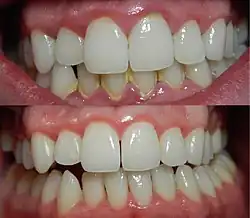

Une gencive saine présente un aspect « en peau d'orange », rose pâle, et ne saigne pas au contact. Lors de la gingivite, la gencive devient rouge (toute variation de couleur signe une situation pathologique), lisse et gonflée. Elle saigne facilement, soit lors du brossage, soit parfois même spontanément. On peut observer des poches parodontales, c'est-à-dire un espace qui se forme entre le haut de la gencive et le niveau où elle s'attache à l'os.

Ses signes sont : rougeur ; œdème (papilles boursouflées) ; gencive brillante, vernissée (la piqueté disparaît) ; saignements fréquents. Il peut y avoir formation de poches parodontales.